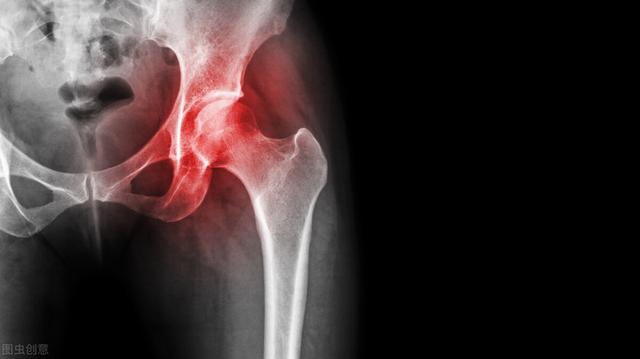

伴随着风湿症状的发展,病人最明显的感觉就是关节像胶水一样坚硬,抬起手臂,弯腰蹲下,这是由于炎症堆积,滑膜增生厚度,导致软安排粘连,骨质钙化或交融所致。若不能及时了解这些部位的肌肉和韧带解开,若选用药物及注射等治疗方法,只能缓解关节疼痛。